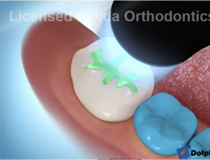

矯正治療を受けられる小児の患者様には、シーラント処置をお勧めしています!

シーラント処置とは、奥歯の噛む面の溝(咬合面)をプラスチックで埋めてしまう処置です。

歯垢が溜まりにくくなる為、虫歯予防の効果があります。

保険適用の処置です(23区内にお住まいの15歳以下の患者様は、無料になります)。

シーラント処置は簡単にみえますが、実は、難しいです!

歯の溝は、奥が深く広がっているので、そこまでしっかりシーラント材を埋める事が重要です。わかりやすいように、シーラント材を緑色にしていますが、実際のシーラント材の色々は、歯と同じ色なので、処置をしてもわかりづらいです。

処置する時には、乾燥が大切です。当院では、ラバーダム防湿という方法のもと、シーラント処置を行っています。ラバーダム防湿とは、処置をする歯だけにラバーをかけて、歯に唾液が付かないようにできる方法です。

「シーラント処置をしたから」といって、もう虫歯にならないと思わないで下さい!

しっかり毎日歯磨きしていきましょう。

① 歯の表面の汚れを取ります

② シーラント材を溝を埋めます

③ 光で固めます